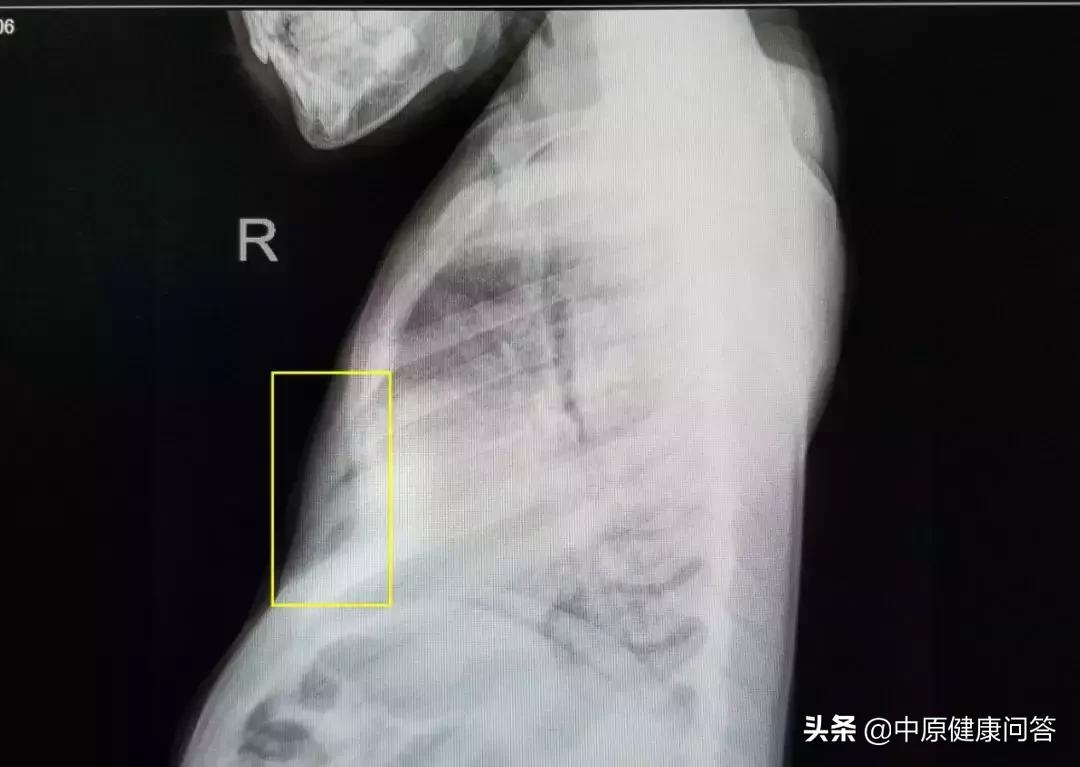

术前胸部侧位片显示小飞胸骨的凹陷程度